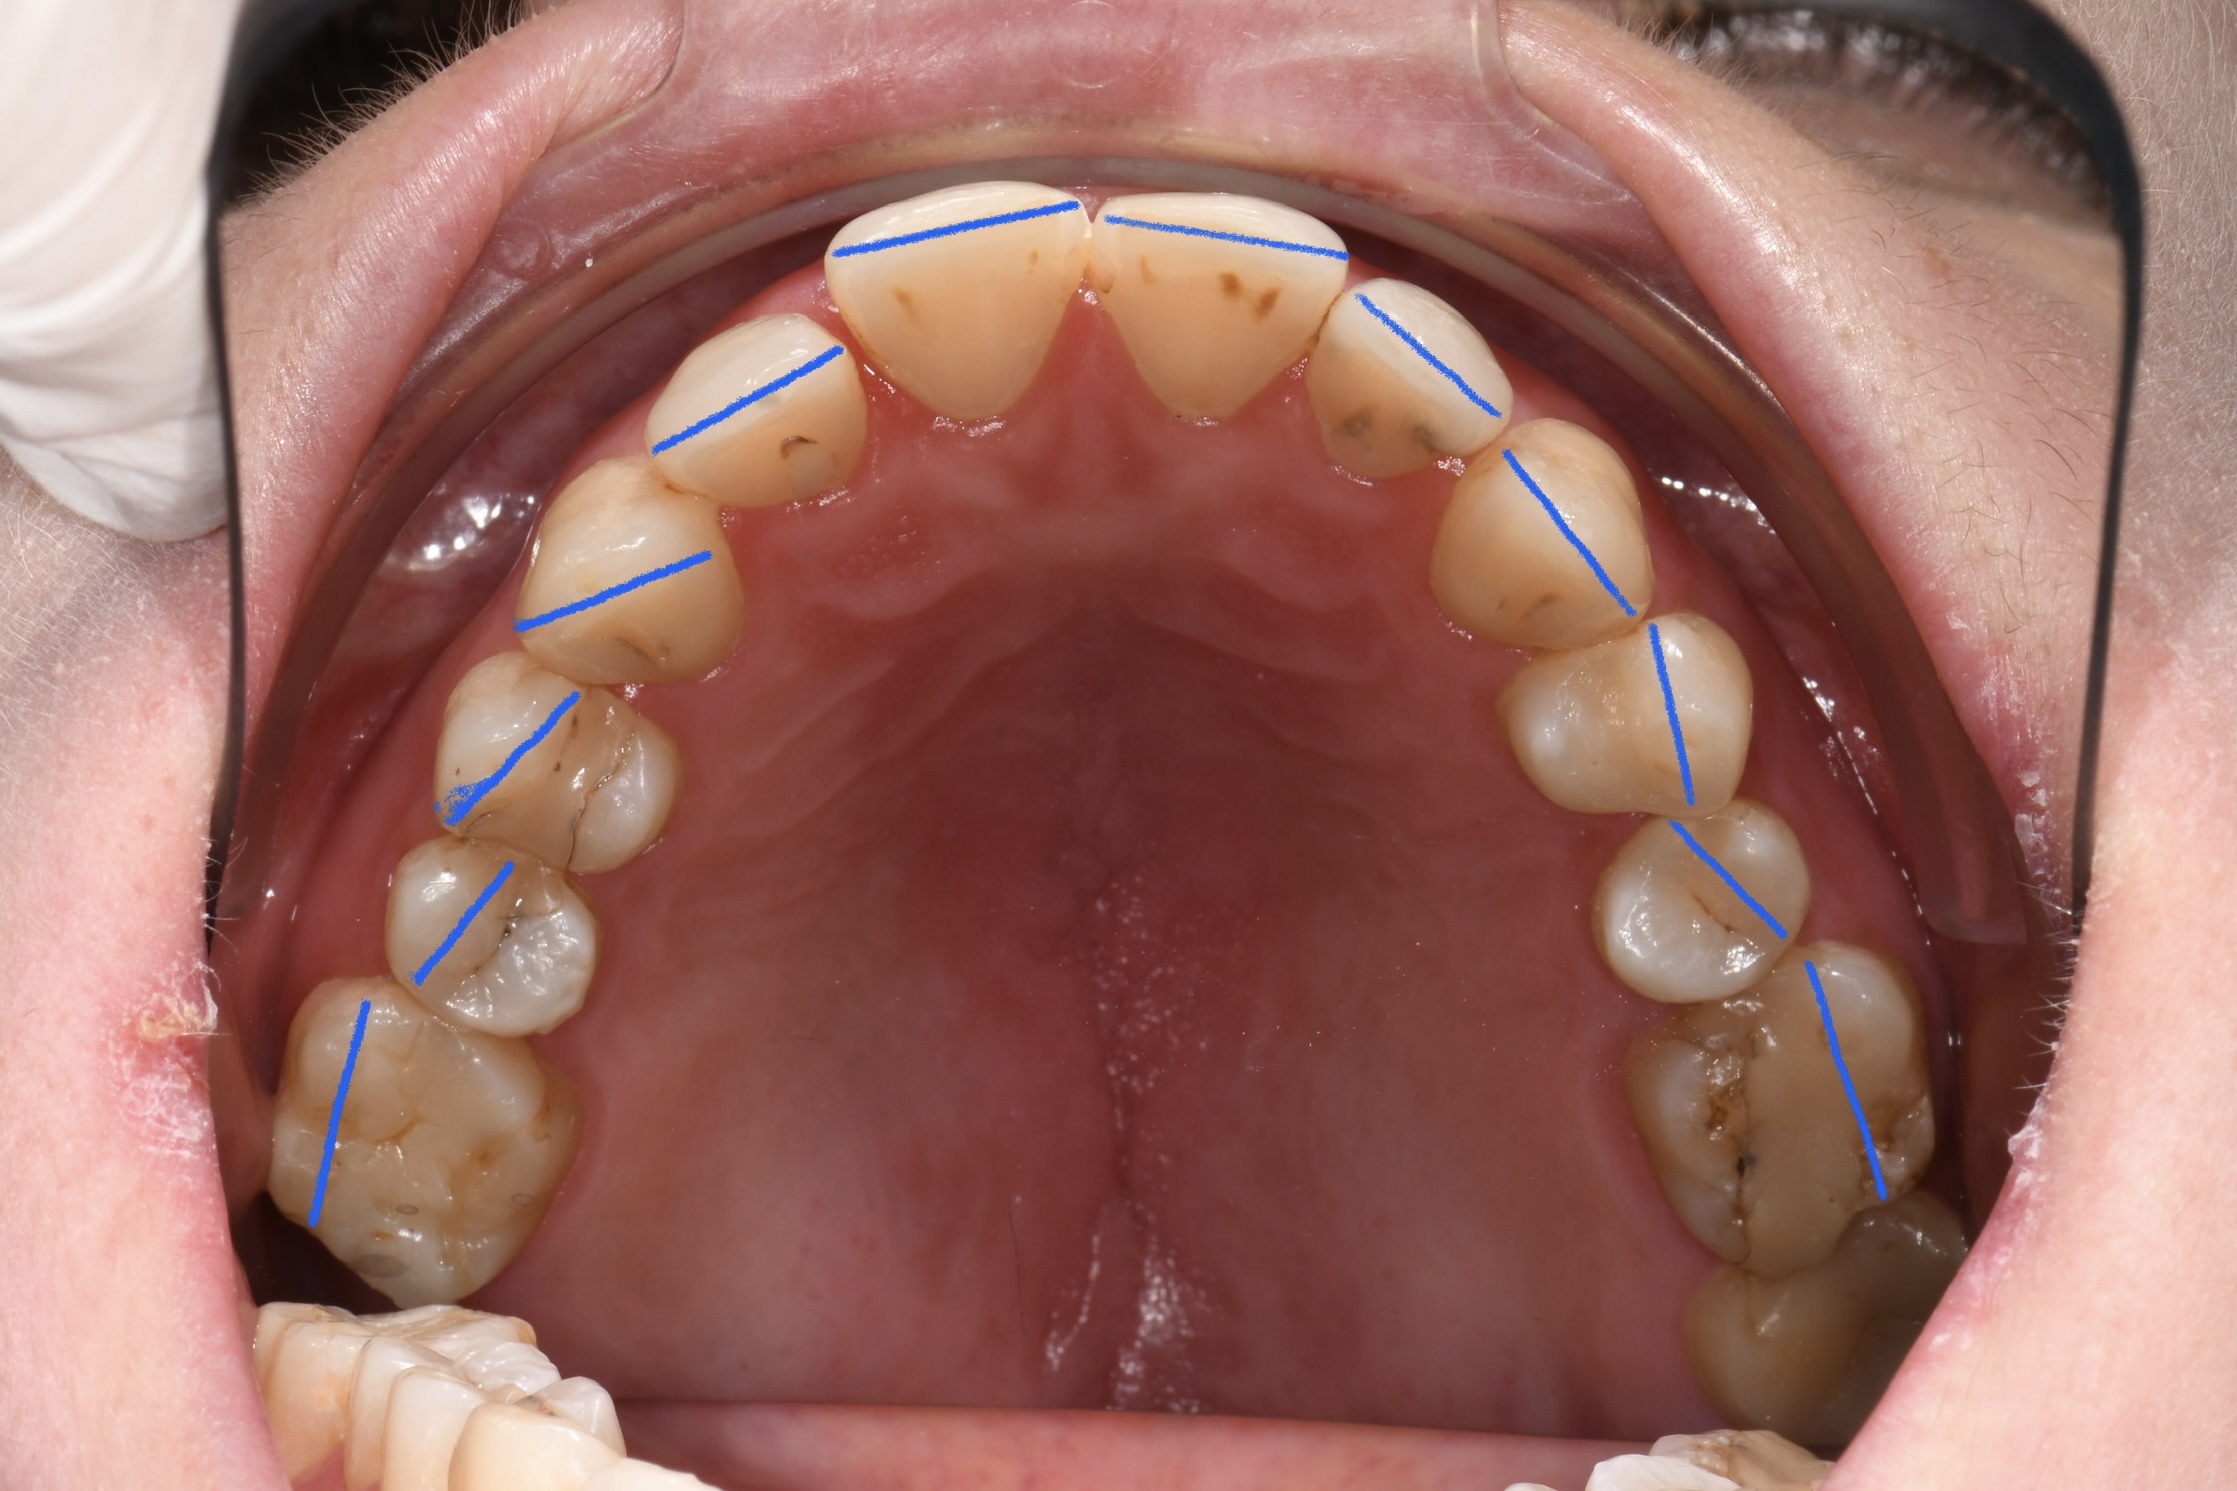

Az elmúlt évekből rengeteg szakmai referenciát tudnánk bemutatni, amelyek különböző fogszabályozási problémákat oldottak meg. Válogatva a több száz esetből, ezen az oldalon olyan képeket, információkat igyekeztünk bemutatni, amelyeknek a segítségével a jövőbeni pácienseinknek azt tudjuk üzenni: A Te fogsorod is lehet gyönyörű!

(Képeket a Pácienseink külön írásos beleegyezésével mutatjuk be!)